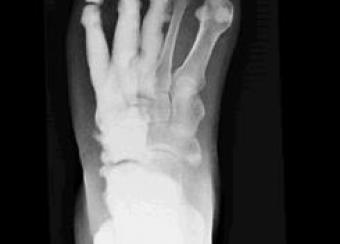

Dr. Bhattacharyya is coordinating a multidisciplinary group investigating the rare bone disease melorheostosis. Research spans the spectrum from seeing patients to genetics to developing cellular models. Two somatic mutations have been identified that cause melorheostosis.

The rare disease melorheostosis causes bones to thicken. This may lead to pain, and can affect bones, joints, and muscles. Researchers want to learn more about the disease and how it progresses.